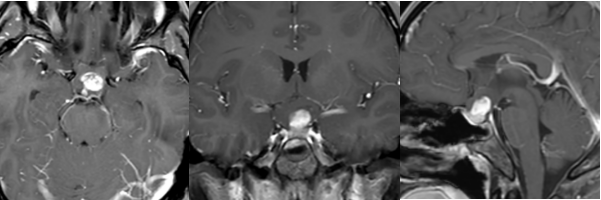

4、CT掃描:可為單側(cè)發(fā)病,也可為雙側(cè)發(fā)病,后者常伴發(fā)神經(jīng)纖維瘤病,并且兩側(cè)發(fā)病順序可不一致,應(yīng)引起重視。視神經(jīng)增粗扭曲為視神經(jīng)膠質(zhì)瘤較常見的表現(xiàn)。由于腫瘤壓迫,常使其前端的正常蛛網(wǎng)膜下腔擴(kuò)大。視神經(jīng)膠質(zhì)瘤眶內(nèi)部分為視神經(jīng)梭形或橢圓性腫大,也可呈管狀增粗,邊界清楚,密度均勻,腫瘤內(nèi)常見低密度的囊變區(qū)。約3%的腫瘤內(nèi)可見鈣化。

5、MRI檢查:表現(xiàn)為視神經(jīng)呈梭形、冠狀或橢圓形增粗,多數(shù)為中心性,少數(shù)為偏心形。與正常眼外肌比較,視神經(jīng)膠質(zhì)瘤在T1WI呈低信號(hào),T2WI呈高信號(hào),增強(qiáng)后中度強(qiáng)化。部分腫瘤壓迫使其前部正常的蛛網(wǎng)膜下腔擴(kuò)大,表現(xiàn)為與腦脊液信號(hào)相似的長T1、長T2信號(hào);由于少數(shù)腫瘤周圍蛛網(wǎng)膜等結(jié)構(gòu)反應(yīng)性增生而形成假性包膜,表現(xiàn)為長T1、長T2 。